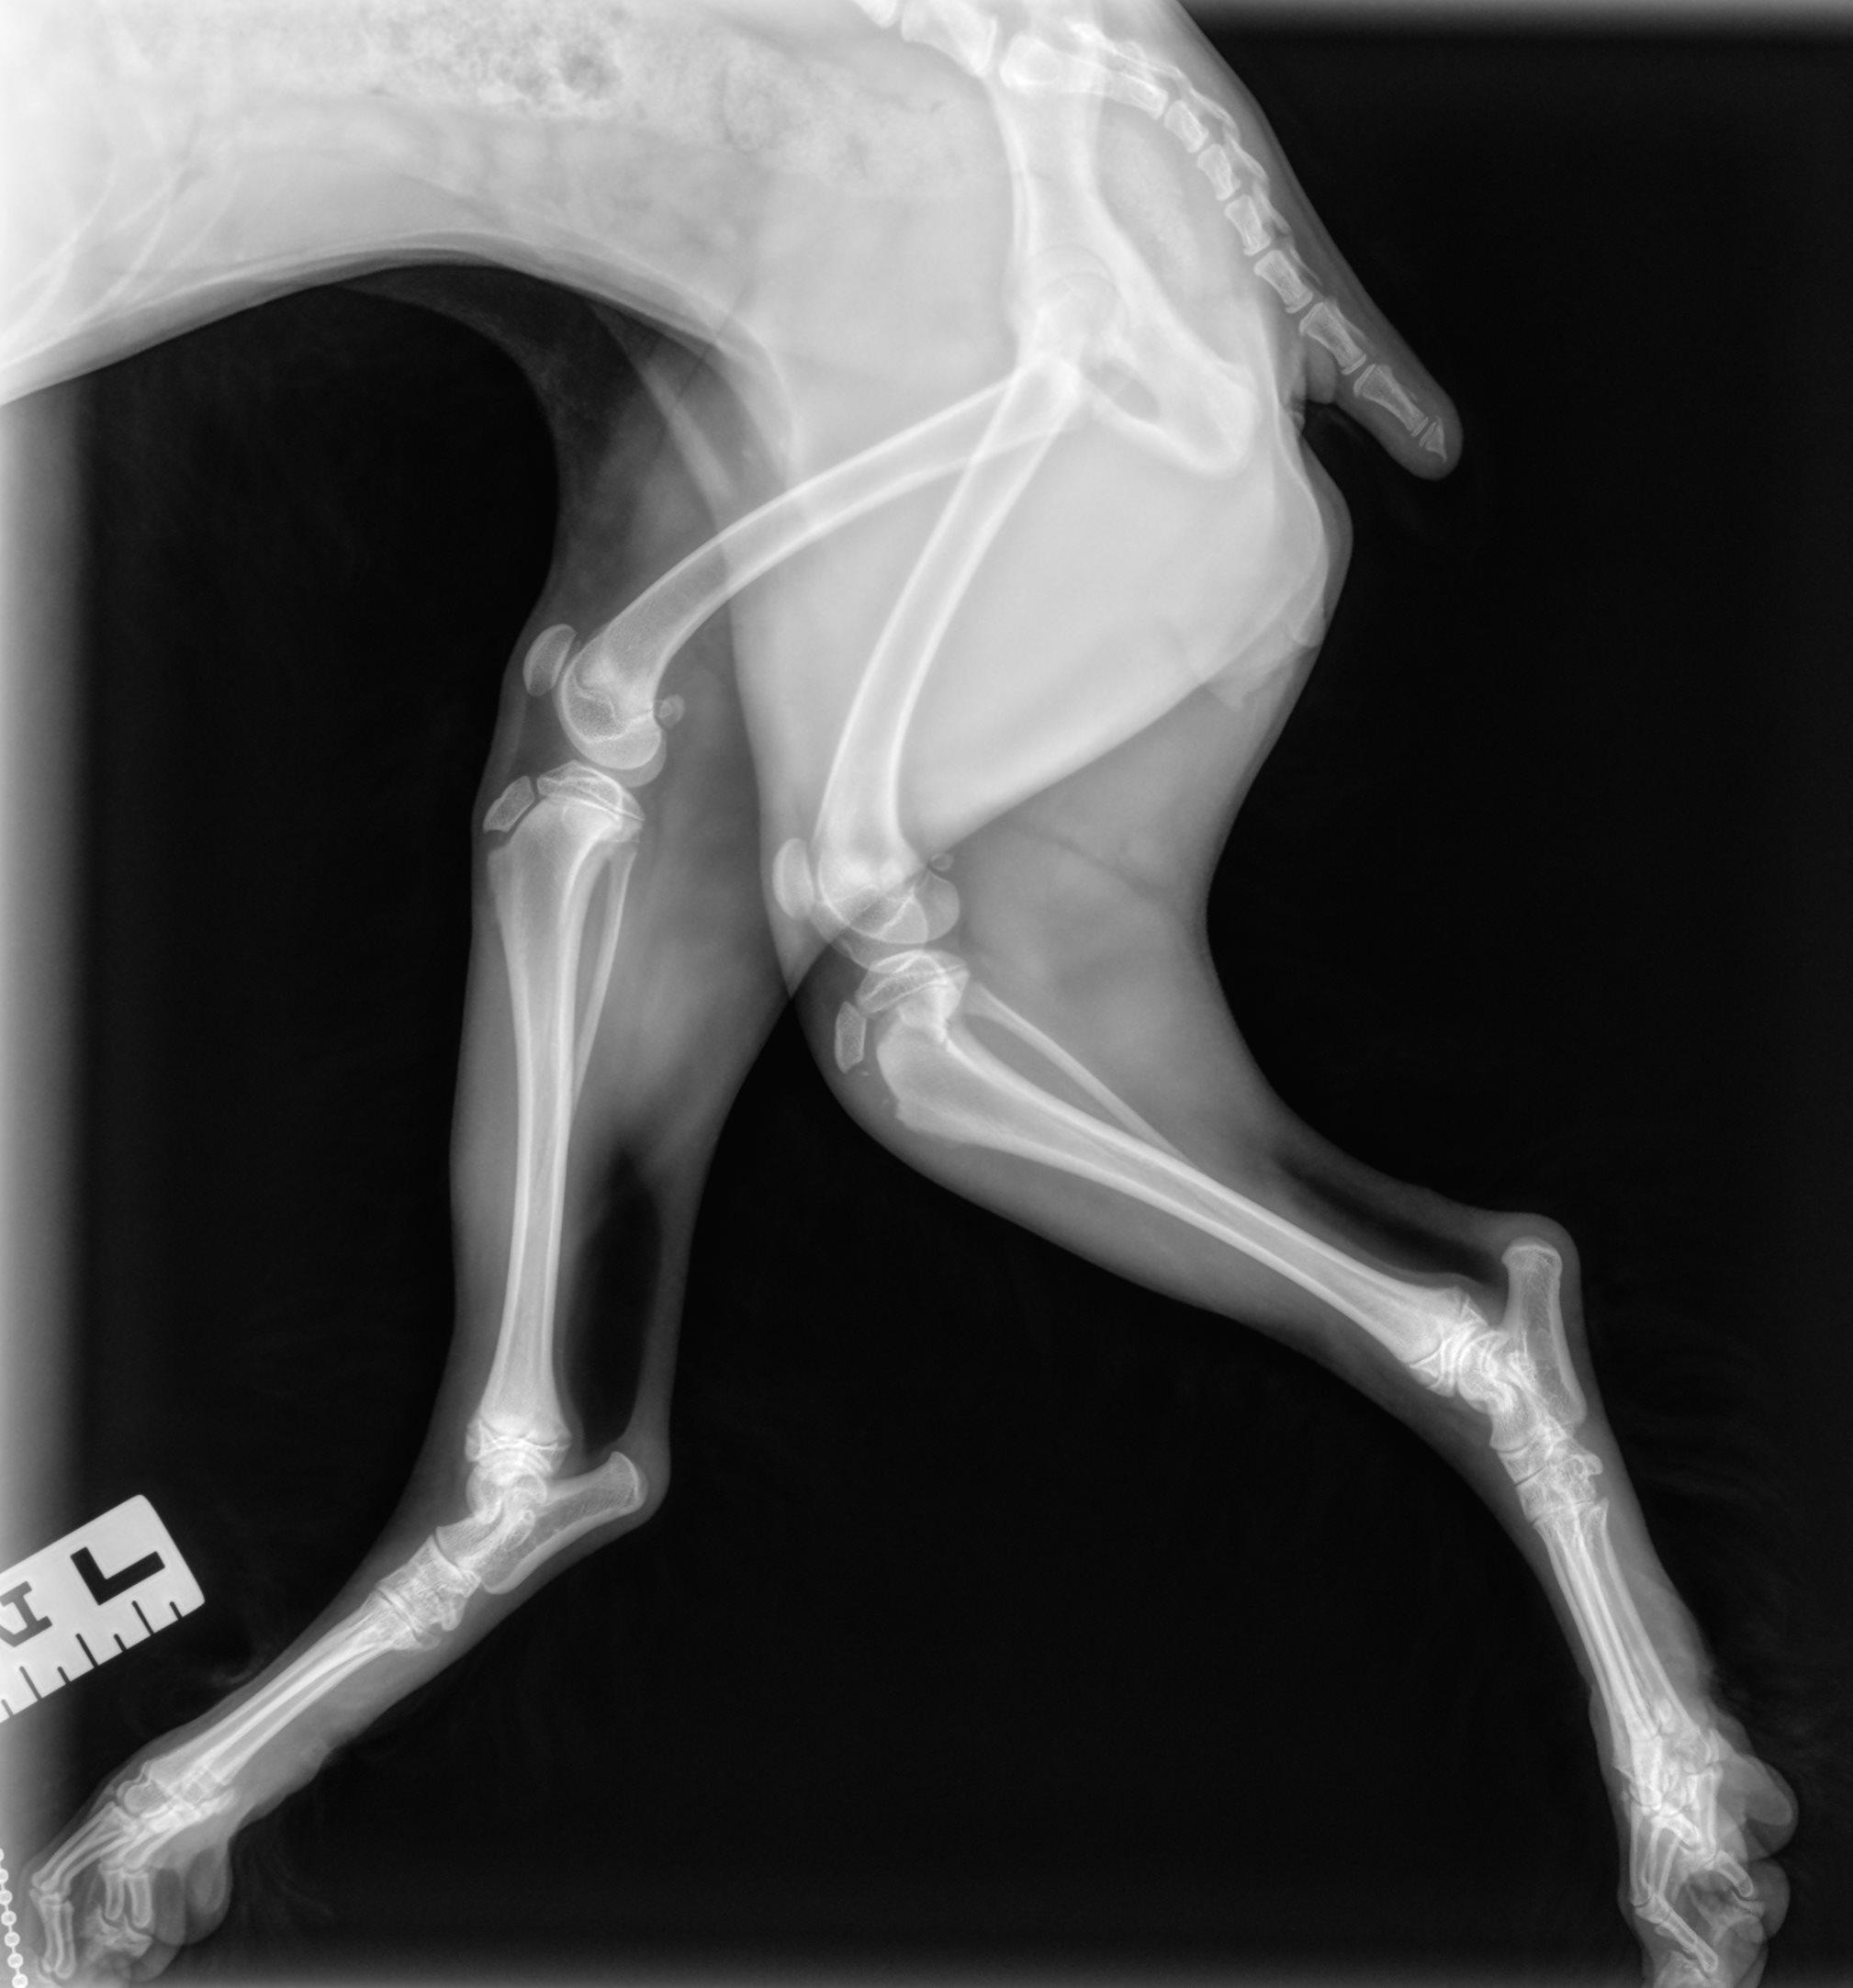

Hieronder vind je de 3 röntgenfoto’s van de achterpoten en bekken. Gebruik de pijltjes om erdoor te schuiven, of klik op de foto om te vergroten.

Er is een avulsiefractuur van de tuberositas tibiae aan de rechterpoot. De tuberositas tibiae is proximaal verplaatst en er zijn minstens enkele kleine botfragmenten zichtbaar ter hoogte van de fractuurplaats. Gelijktijdig is er een Salter-Harris type II fractuur van het caudo-proximale deel van de tibia, het best zichtbaar op de laterale opname. Het overige deel van de achterpoten is radiografisch binnen de normale grenzen.

Avulsiefractuur van de rechter tuberositas tibiae met kleine botfragmenten. Chirurgisch consult wordt aanbevolen.